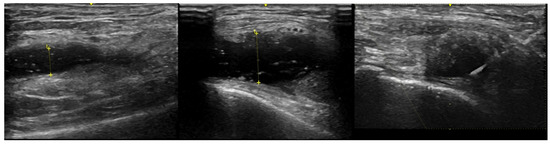

- Meehan, R.; Wilson, C.; Hoffman, E.; Altimier, L.; Kaessner, M.; Regan, E.A. Ultrasound measurement of knee synovial fluid during external pneumatic compression. J. Orthop. Res. 2019, 37, 601–608. [Google Scholar] [CrossRef] [PubMed]